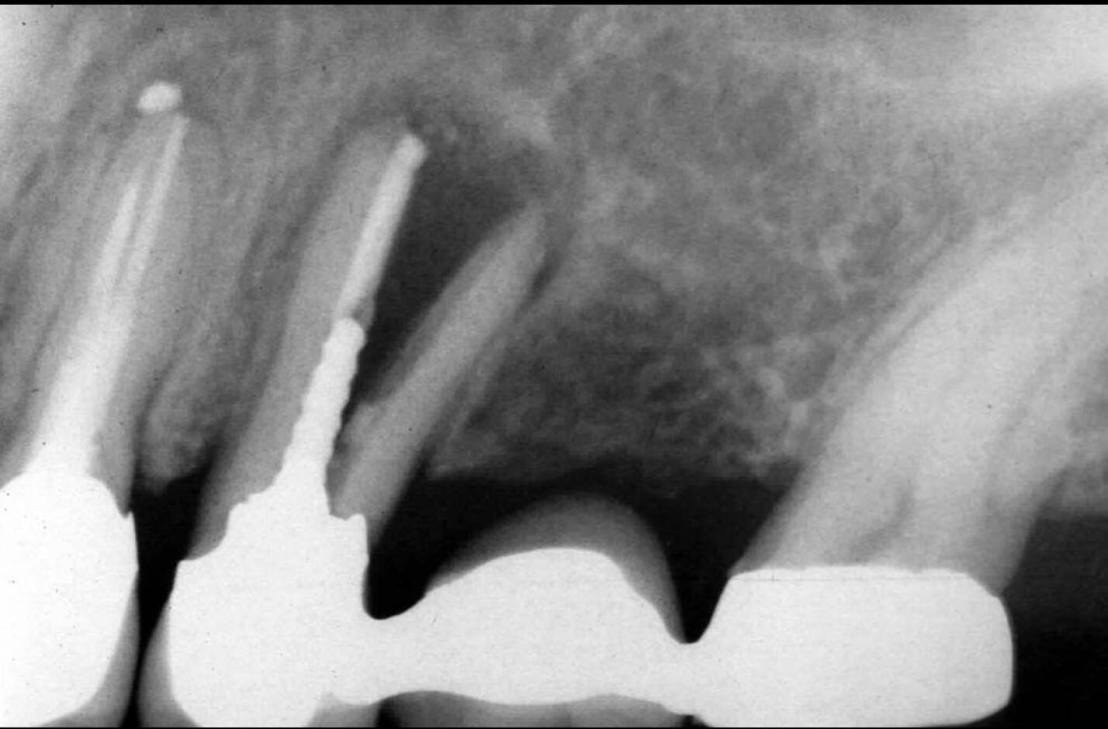

film Pa ฟิล์มนี้ก็นำมาจากบทเดียวกันครับ

ท่านอาจารย์ผู้เขียนอาจจะมีประสบการณ์เจอเคสแบบในฟิลม์นี้มาเยอะ เลย recommend ให้ใช้ Post&Core ในกรณีที่จำเป็นเท่านั้น คือ Pt มีแรงกัดสูงกว่าปกติ หรือ ฟันที่ถูกทำลายจนไม่มี Ferrule เหลืออยู่เลยเท่านั้นครับ